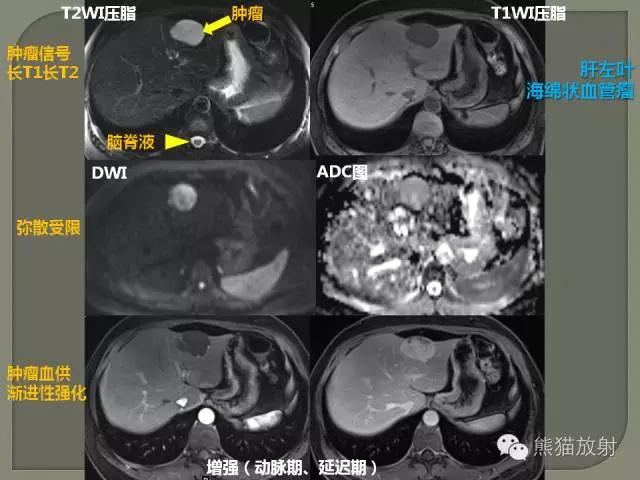

3、水为长T1长T2,脂肪为短T1长T2。

4、长T1为低信号(暗),短T1为高信号(亮)。

5、长T2为高信号(亮),短T2为低信号(暗)。

T1加权像 短TR、短TE——T1加权像,T1像特点:组织的T1越短,恢复越快,信号就越强;组织的T1越长,恢复越慢,信号就越弱。

T2加权像 长TR、长TE——T2加权像, T2像特点:组织的T2越长,恢复越慢,信号就越强;组织的T2越短,恢复越快,信号就越弱。

水 肿: 无论何种类型水肿,细胞内或组织间隙内的含水量增加,均使T1值和T2值延长,Pd值降低,故在T1WI和PDWI图像上水肿区呈较低信号,而在T2WI图像上则呈明显的高信号,对比鲜明。